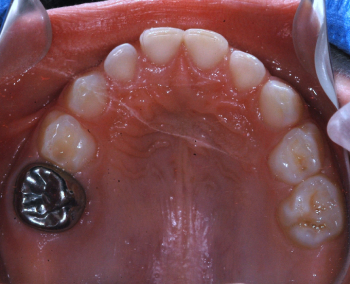

Después: